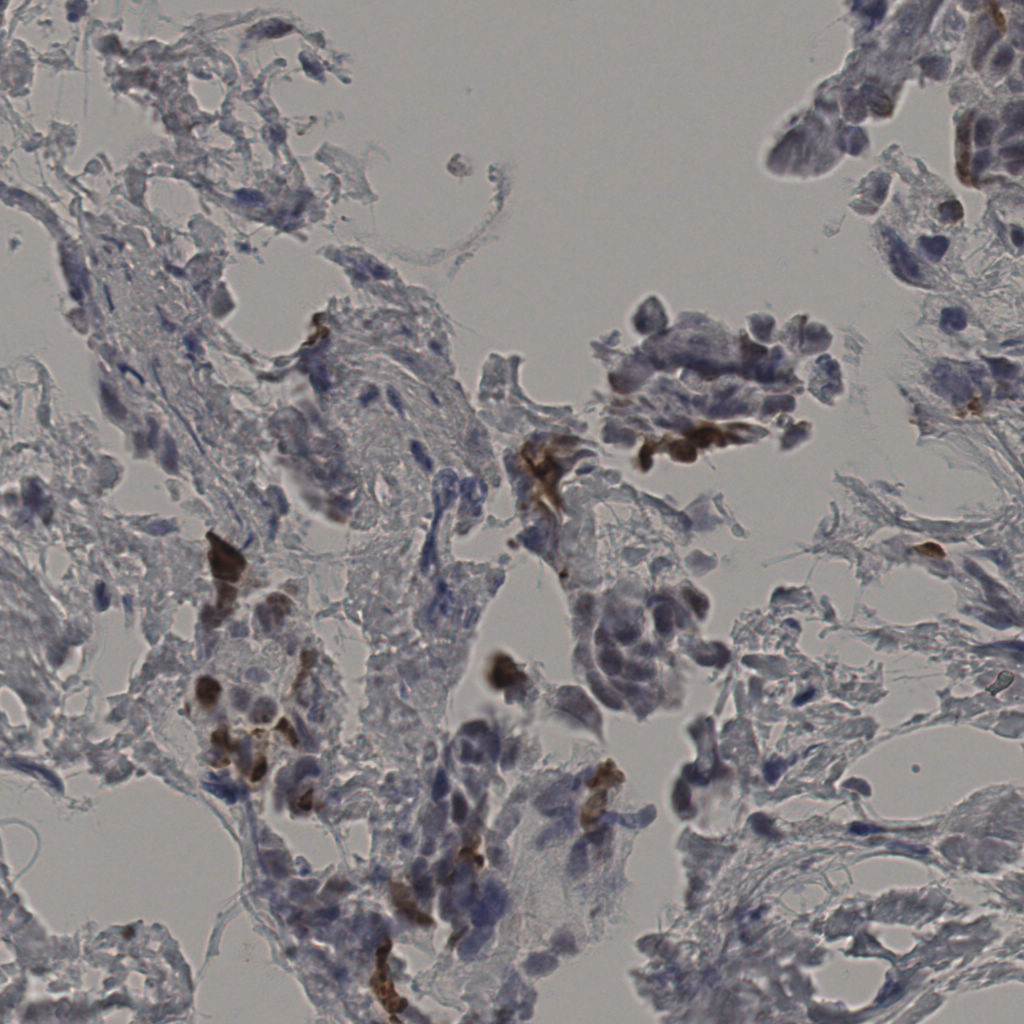

缩略图

标记后

标记前